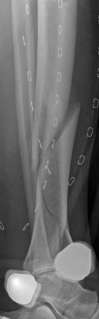

The management of complex tibial shaft fractures with extension into the distal articular surface (the tibial plafond or pilon) represents one of the most formidable challenges in orthopedic traumatology. These injuries typically result from high-energy mechanisms, such as a fall from a significant height or a motor vehicle collision, where axial loading forces are combined with severe rotational and shear vectors. The classic presentation, as highlighted in our index case of a 26-year-old male who fell 3 meters into a hole, involves not only catastrophic bony disruption but also devastating injury to the surrounding soft tissue envelope. The delicate nature of the soft tissues in the distal third of the leg, characterized by sparse muscular coverage and a precarious vascular supply, dictates the entire trajectory of clinical decision-making.

When a diaphyseal fracture propagates into the distal articular block, the injury transcends the typical treatment algorithms reserved for isolated tibial shaft fractures. Intramedullary nailing, the gold standard for diaphyseal fractures, becomes fraught with complications such as articular malreduction, propagation of intra-articular fracture lines, and inadequate distal fixation. Therefore, plate fixation—often utilizing minimally invasive percutaneous plate osteosynthesis (MIPPO) techniques—emerges as the primary definitive treatment modality. In the setting of an AO/OTA 43C3.3 fracture, where the articular surface is multifragmentary and completely dissociated from the diaphysis, the surgeon must meticulously reconstruct the joint surface before bridging the diaphyseal segment.

The patho-epidemiology of these injuries is inextricably linked to the incidence of acute compartment syndrome. High-energy axial loads result in rapid swelling, hemorrhage, and edema within the unyielding fascial compartments of the leg. As demonstrated in our reference case, clinical examination often reveals a tense, swollen limb necessitating an immediate four-compartment fasciotomy. The dual-incision technique remains the standard of care to decompress the anterior, lateral, superficial posterior, and deep posterior compartments. The presence of fasciotomy wounds further complicates the surgical approach for definitive internal fixation, requiring strict adherence to the principles of damage control orthopedics (DCO).

Initial management in these high-velocity scenarios mandates the application of a spanning external fixator to achieve skeletal traction, restore length, and allow the soft tissue envelope to recover. This temporary stabilization minimizes ongoing secondary soft tissue trauma from mobile fracture fragments. However, the application of external fixators is not without risk; meticulous pin placement is required. For instance, calcaneal transfixion pins must be placed with strict attention to the neurovascular bundle to avoid iatrogenic tibial nerve irritation, an issue that required revision in the early phase of our index patient's care.